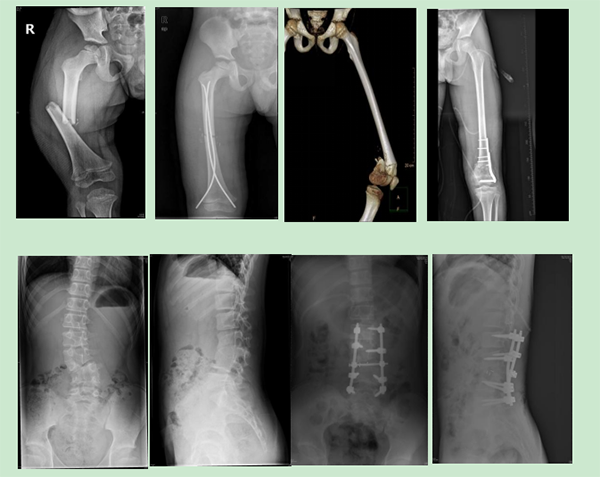

徐醫(yī)附院小兒骨科依托省級臨床重點?乒强破脚_,擁有雄厚的醫(yī)療、科研實力,配備了脊柱手術(shù)顯微鏡、術(shù)中導航、脊柱微創(chuàng)內(nèi)鏡、關(guān)節(jié)鏡設備、術(shù)中神經(jīng)電生理監(jiān)測、超聲骨刀等先進設備,極大地保證了患兒高難手術(shù)的精準性和安全性。自2022年2月17日成立以來,徐醫(yī)附院小兒骨科秉承“微創(chuàng)化、精準化”的治療原則,為淮海經(jīng)濟區(qū)兒童骨科患者提供優(yōu)質(zhì)的醫(yī)療服務,贏得了廣泛贊譽。當前,徐醫(yī)附院小兒骨科每月完成手術(shù)近40余臺。小兒肱骨髁上骨折、前臂骨折、股骨干骨折等常見骨折基本上都是經(jīng)皮微創(chuàng)完成,獲得患兒家長的好評和信任。